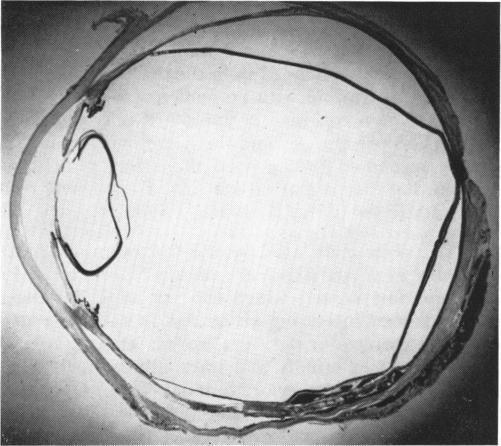

Intraocular biopsy: an evaluation.

Trans Am Ophthalmol Soc. 1952;50:375-405.